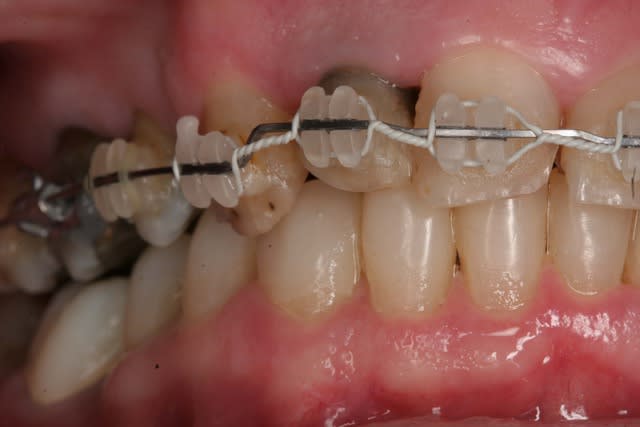

Donc la suite, évidement ortho: ingression du bloc incisivo canin sup avec ré alignement des arcades, extraction de la 14 nécessaire et ré alignement des milieux interincisif.

Pendant la finalisation du haut (axe mésio-disto incisif, à corriger à la fin pour faciliter gingivoplastie incisif sup). Il y a eu composite vestibulaire pelliculaire sous digue de 33 à 43, reprise soins et ancrage + provisoires 34,35, 36, 46; et composite sous digue 37 et 47.